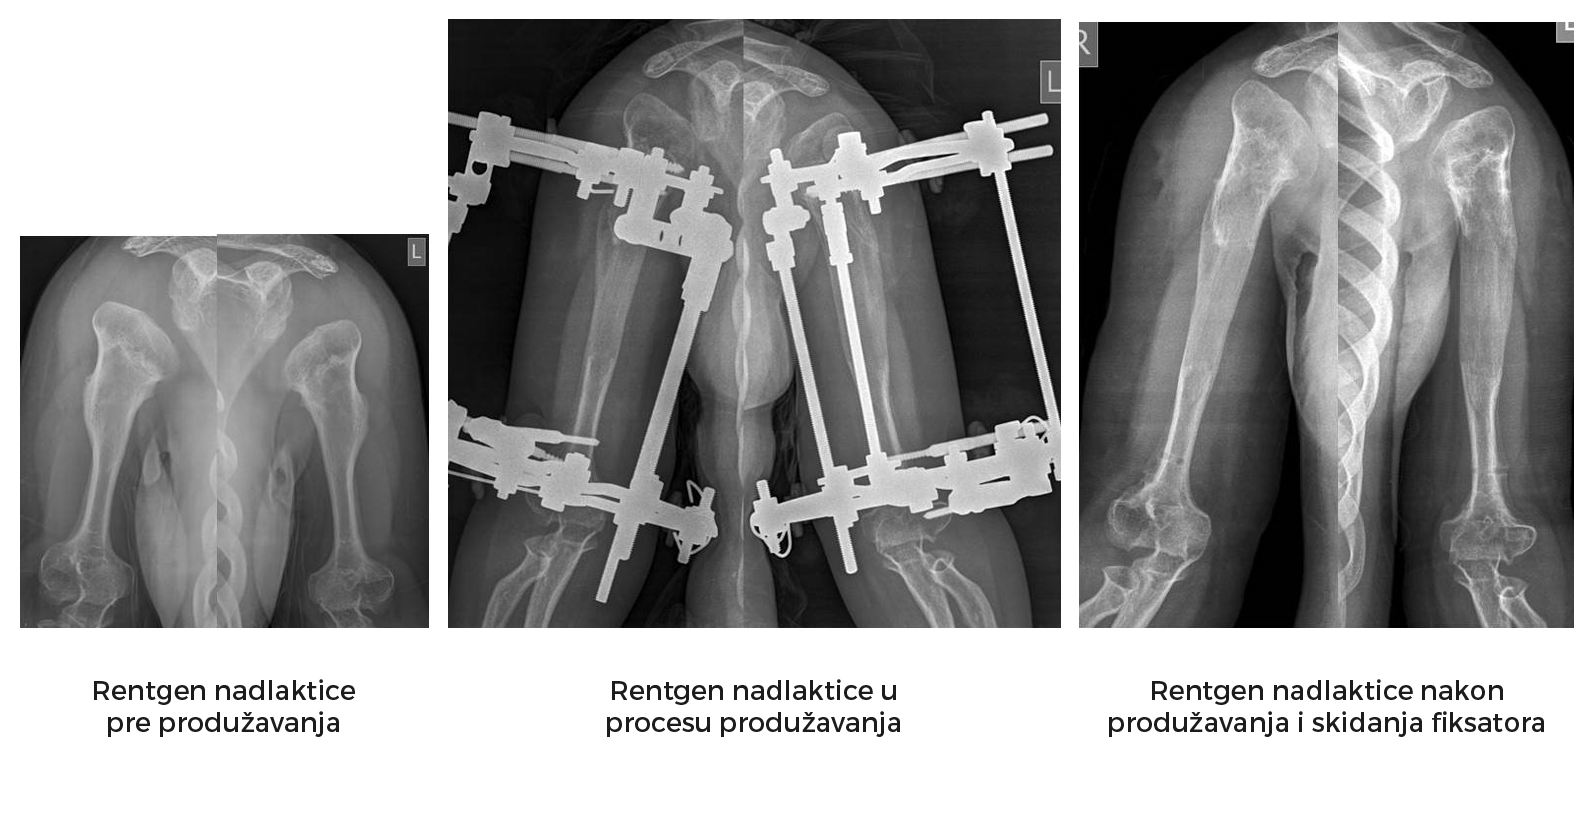

Slede primeri takve rekonstrukcije ekstremiteta (iz arhive prof. D. Popkova i Atlas klinike).

*Etapa produžavanje nadlaktice.